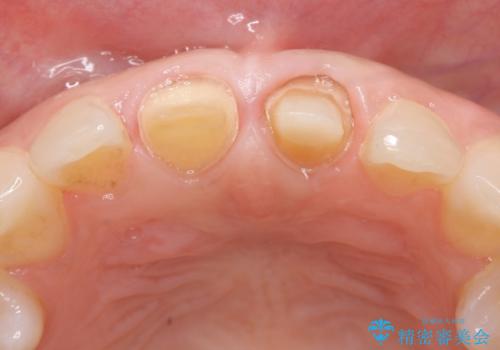

- 前歯の変色が気になるのでセラミックによる治療を行いたいといらっしゃった方の症例です。

左上1番目の歯の再根管治療終了後、左右1番目の2歯をオールセラミッククラウンで補綴しました。

- オールセラミッククラウン…¥100,000×2、仮歯…¥10,000×2、ファイバーコア…¥20,000費用は治療当時の料金となります